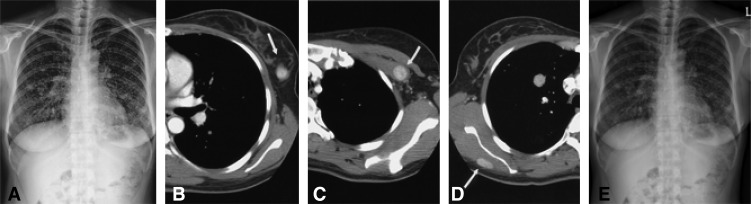

Figure 1

Radiologic findings of benign metastasizing leiomyoma in a 39-year-old woman. The chest radiograph (A) shows multiple, variable-sized nodules in both lungs, suggesting hematogenous metastasis. Chest CT scans with intravenous contrast enhancement demonstrate multiple, well-enhancing masses in the left breast (B, arrow), the left pectoralis minor muscle (C, arrow), and the right infraspinatus muscle (D, arrow). The follow-up chest radiography (E) showed the decreased size of the multiple nodular lesions.

The chest radiograph showed multiple, variable-sized nodules in both lungs, suggesting hematogenous metastasis (Figure 1A). Chest CT scans with intravenous contrast enhancement demonstrated multiple well-enhancing masses in both breasts (Figure 1B), the left pectoralis minor muscle (Figure 1C), and the right infraspinatus muscle (Figure 1D). A CT scan obtained with a lung window setting showed multiple variable-sized nodules in both lungs, which suggested hematogenous metastasis (not shown).

After surgical hormonal ablation, she was prescribed tamoxifen. Follow-up chest radiography (Figure 1E) showed the decreased size of the multiple nodular lesions. This response has been sustained until the present.